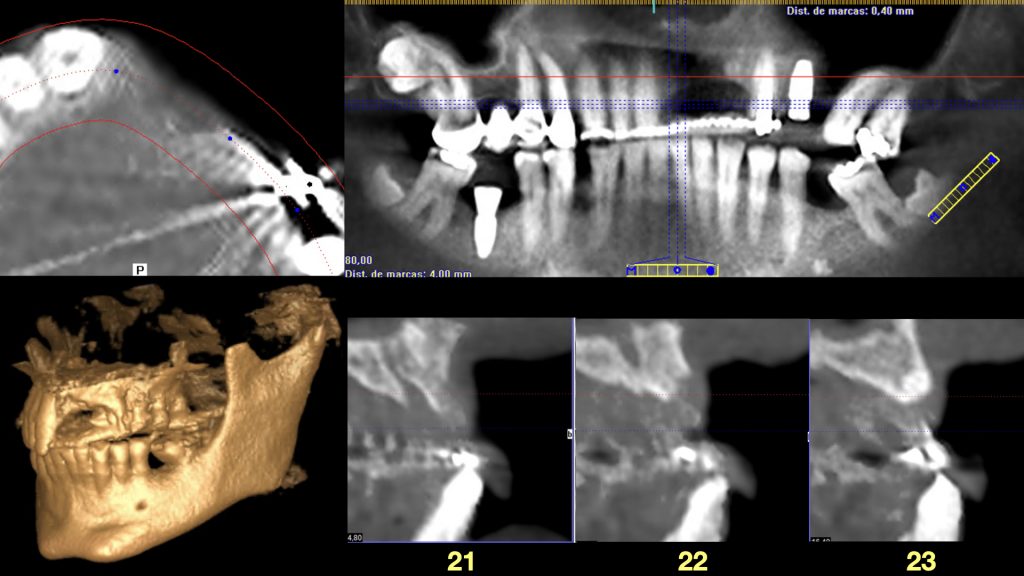

A la exploración radiográfica se observa la pérdida ósea interproximal de los 3 implantes confirmándose así el diagnóstico de periimplantitis (Figura 2).

Radiografía 3D donde se puede apreciar la atrofia ósea.